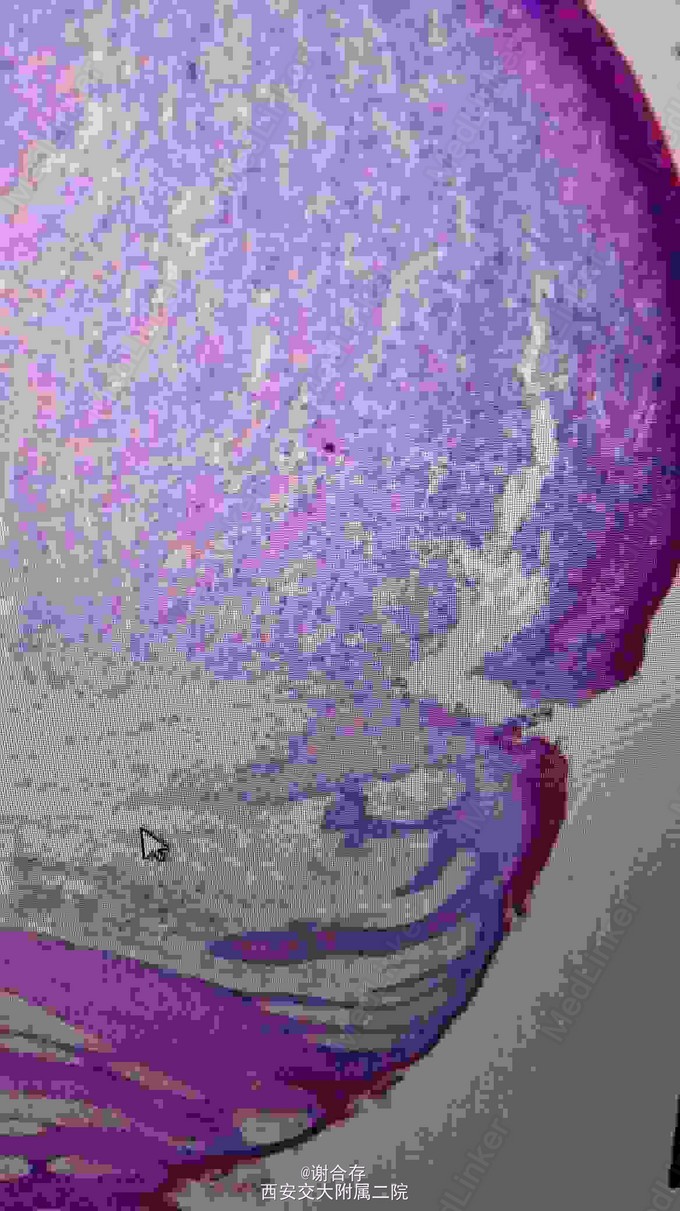

皮损处组织病理: 真皮层内可见弥漫性淋巴样肿瘤细胞浸润,细胞体积大, 核仁大,异型性明显,核分裂像多见,可见瘤巨细胞。诊断: 皮肤间变性大细胞淋巴瘤。采用CHOP 方案( 第1 天静脉注射环磷酰胺800mg;表柔比星40mg, 第1 天 第2 天静脉注射; 长春新碱1.5mg, 第1 天 第8 天静脉注射;泼尼松40mg, 第1 至10 天 口服) 进行化疗,第一疗程结束后肿块消退明显,3周后拟行第二次化疗。